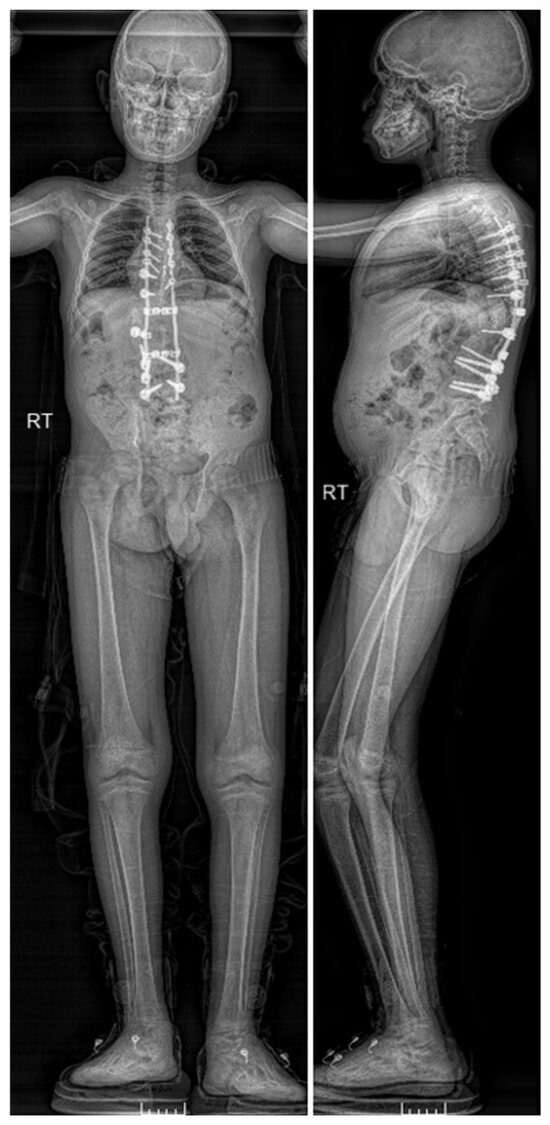

Figure 9.

Full-length AP and lateral EOS images—4-months Post-operatively.

Postoperative CT scan images verified bone formation across the congenital defect, and clinically, he was balanced in both sagittal and coronal planes (Figure 9, Figure 10, Figure 11 and Figure 12).